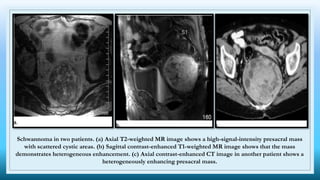

Schwannoma in two patients. (a) Axial T2-weighted MR image shows a high-signal-intensity presacral mass

with scattered cystic areas. (b) Sagittal contrast-enhanced T1-weighted MR image shows that the mass

demonstrates heterogeneous enhancement. (c) Axial contrast-enhanced CT image in another patient shows a

heterogeneously enhancing presacral mass.